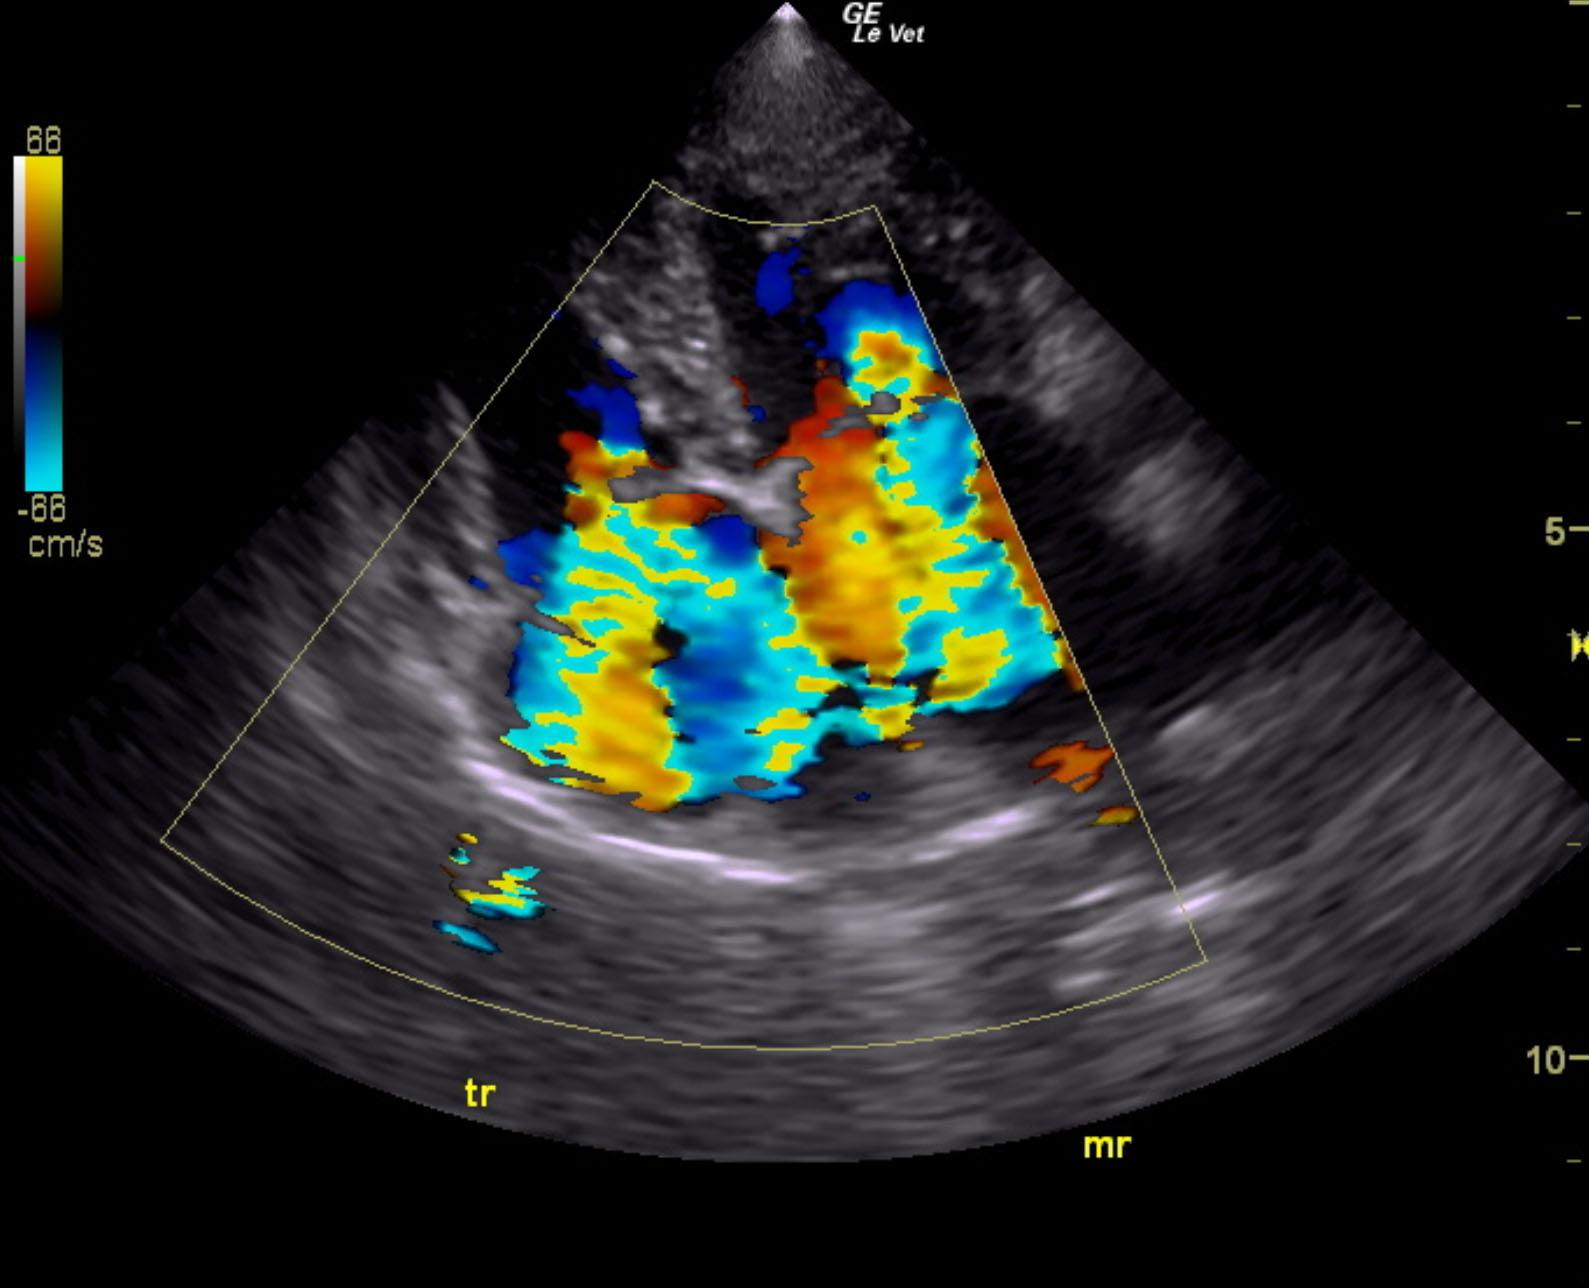

The cardiac presentation revealed moderate left and right sided overload with tricuspid and mitral valve vegetative lesions. Left atrial and right atrial enlargement was noted. Right ventricular overload was noted with flattening of the ventricular septum. Slight prolapse of the anterior mitral valve leaflet was noted. Prolapse of the tricuspid vavle was also noted. Significant pulmonic insufficiency and tricuspid insufficiency was noted. This is consistent with pulmonary hypertension.